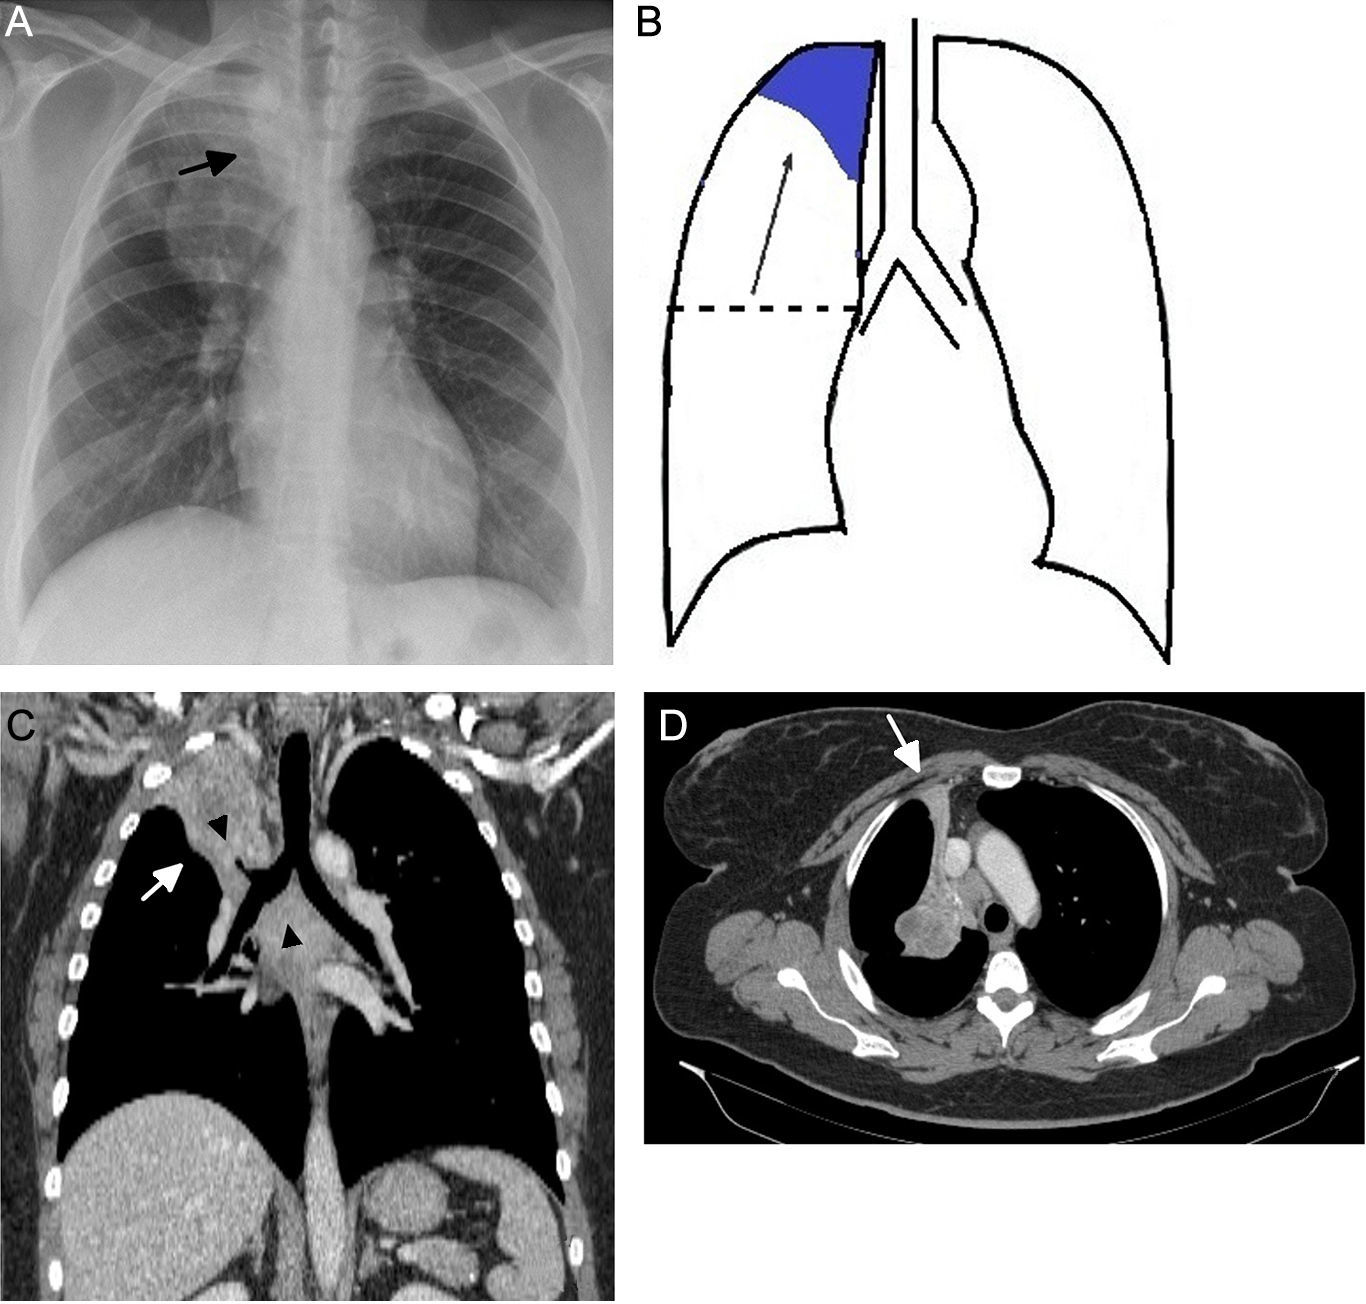

Atelectasis is an important indicator of potentially severe underlying disease that must be diagnosed as early as possible. One of the most common mechanisms is the reabsorption of air distal to respiratory tract obstruction. The chest X-ray is an excellent tool to diagnose atelectasis, and it is especially useful for ruling out central bronchial obstructions (e.g., from endobronchial tumors). If the signs of volume loss are not recognized correctly, the diagnosis and treatment can be delayed. This article describes the main findings of lobar atelectasis on chest X-rays and their correlations with CT findings, including the classic signs described in the literature and other, less known and sometimes subtle signs.